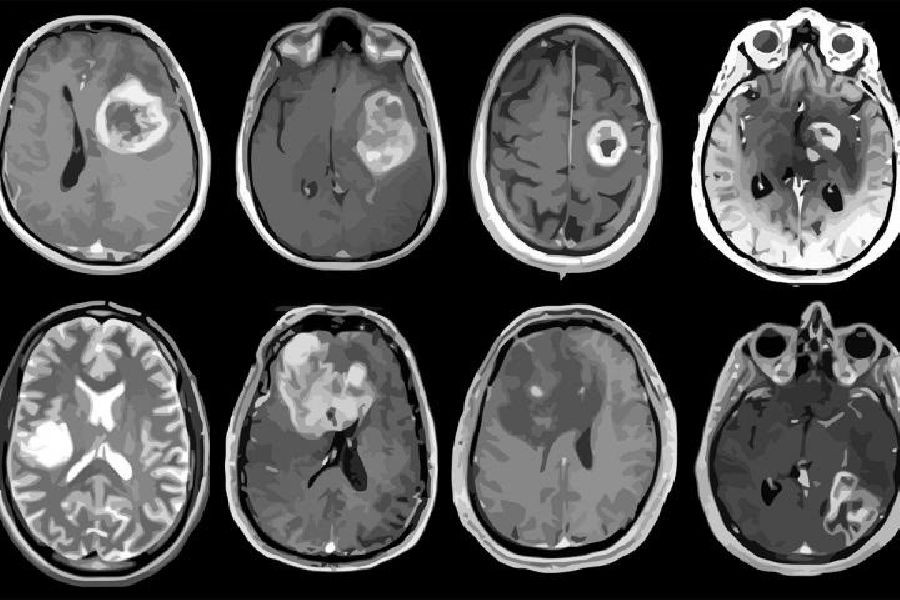

Descubierto nuevo objetivo de inmunoterapia para tumores cerebrales malignos

Los científicos aseguran haber descubierto un nuevo objetivo potencial para la inmunoterapia de los tumores cerebrales malignos, que hasta ahora se han resistido a la inmunoterapia, el innovador tratamiento del cáncer basado en el aprovechamiento del sistema inmunológico del cuerpo. El descubrimiento, publicado en la revista `CELL`, de momento no tiene implicaciones inmediatas para el tratamiento de los pacientes, advierten los investigadores.

Los científicos señalan que la molécula, llamada CD161, es un receptor inhibidor que encontraron en las células T aisladas de muestras frescas de tumores cerebrales llamados gliomas difusos. Los gliomas incluyen el glioblastoma, el tipo de tumor cerebral más agresivo e incurable. El receptor CD161 es activado por una molécula llamada CLEC2D en células tumorales y células inmunodepresoras en el cerebro, según los investigadores. La activación de CD161 debilita la respuesta de las células T contra las células tumorales.

Para determinar si el bloqueo de la vía del CD161 podría restablecer la capacidad de las células T para atacar a las células del glioma, los investigadores la desactivaron de dos maneras: eliminaron el gen llamado KLRB1 que codifica el CD161, y utilizaron anticuerpos para bloquear la vía CD161-CLEC2D.

En un modelo animal de gliomas, esta estrategia aumentó considerablemente la eliminación de las células tumorales por parte de las células T y mejoró la supervivencia de los animales. Los investigadores también se sintieron alentados porque el bloqueo de la vía inhibidora parecía reducir el agotamiento de las células T, una pérdida de la función de eliminación de células en las células T que ha sido un obstáculo importante en la inmunoterapia.

Antes del estudio actual, los investigadores señalan que se sabía poco sobre la expresión de genes y los circuitos moleculares de las células T inmunes que se infiltran en los tumores de glioma, pero no detienen su crecimiento.

Para abrir una ventana en estos circuitos de células T, los investigadores aprovecharon las nuevas tecnologías para leer la información genética en células individuales, un método llamado RNA-seq de célula única. Aplicaron RNA-seq a células T infiltrantes de glioma de muestras de tumores recientes de 31 pacientes y crearon un "atlas" de vías que regulan la función de las células T. Al analizar los datos de RNA-seq, los investigadores identificaron la proteína CD161, codificada por el gen KLRB1, como un receptor inhibidor potencial.

Esta estrategia se probó en dos modelos animales diferentes creados mediante la implantación de "gliomasferas" (grupos tridimensionales de células tumorales de pacientes humanos) en roedores, que desarrollaron tumores agresivos que invadieron el cerebro. Posteriormente, los científicos inyectaron células T con el gen KLRB1 editado en el líquido cefalorraquídeo de algunos de los animales y células T a las que no se les había eliminado el gen KLRB1.

La transferencia de las células T editadas genéticamente ralentizó el crecimiento de los tumores y "confirió un beneficio de supervivencia significativo" en ambos modelos animales de gliomas, apunta los científicos.